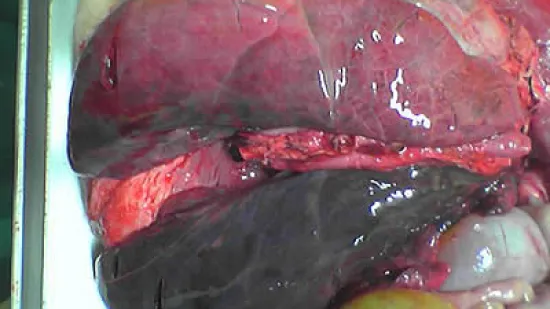

Ce porc de 50 kg est mort de streptococcie (Streptococcus suis 2) et voici l'aspect de ses poumons à l'autopsie. Qu'en dites vous ?